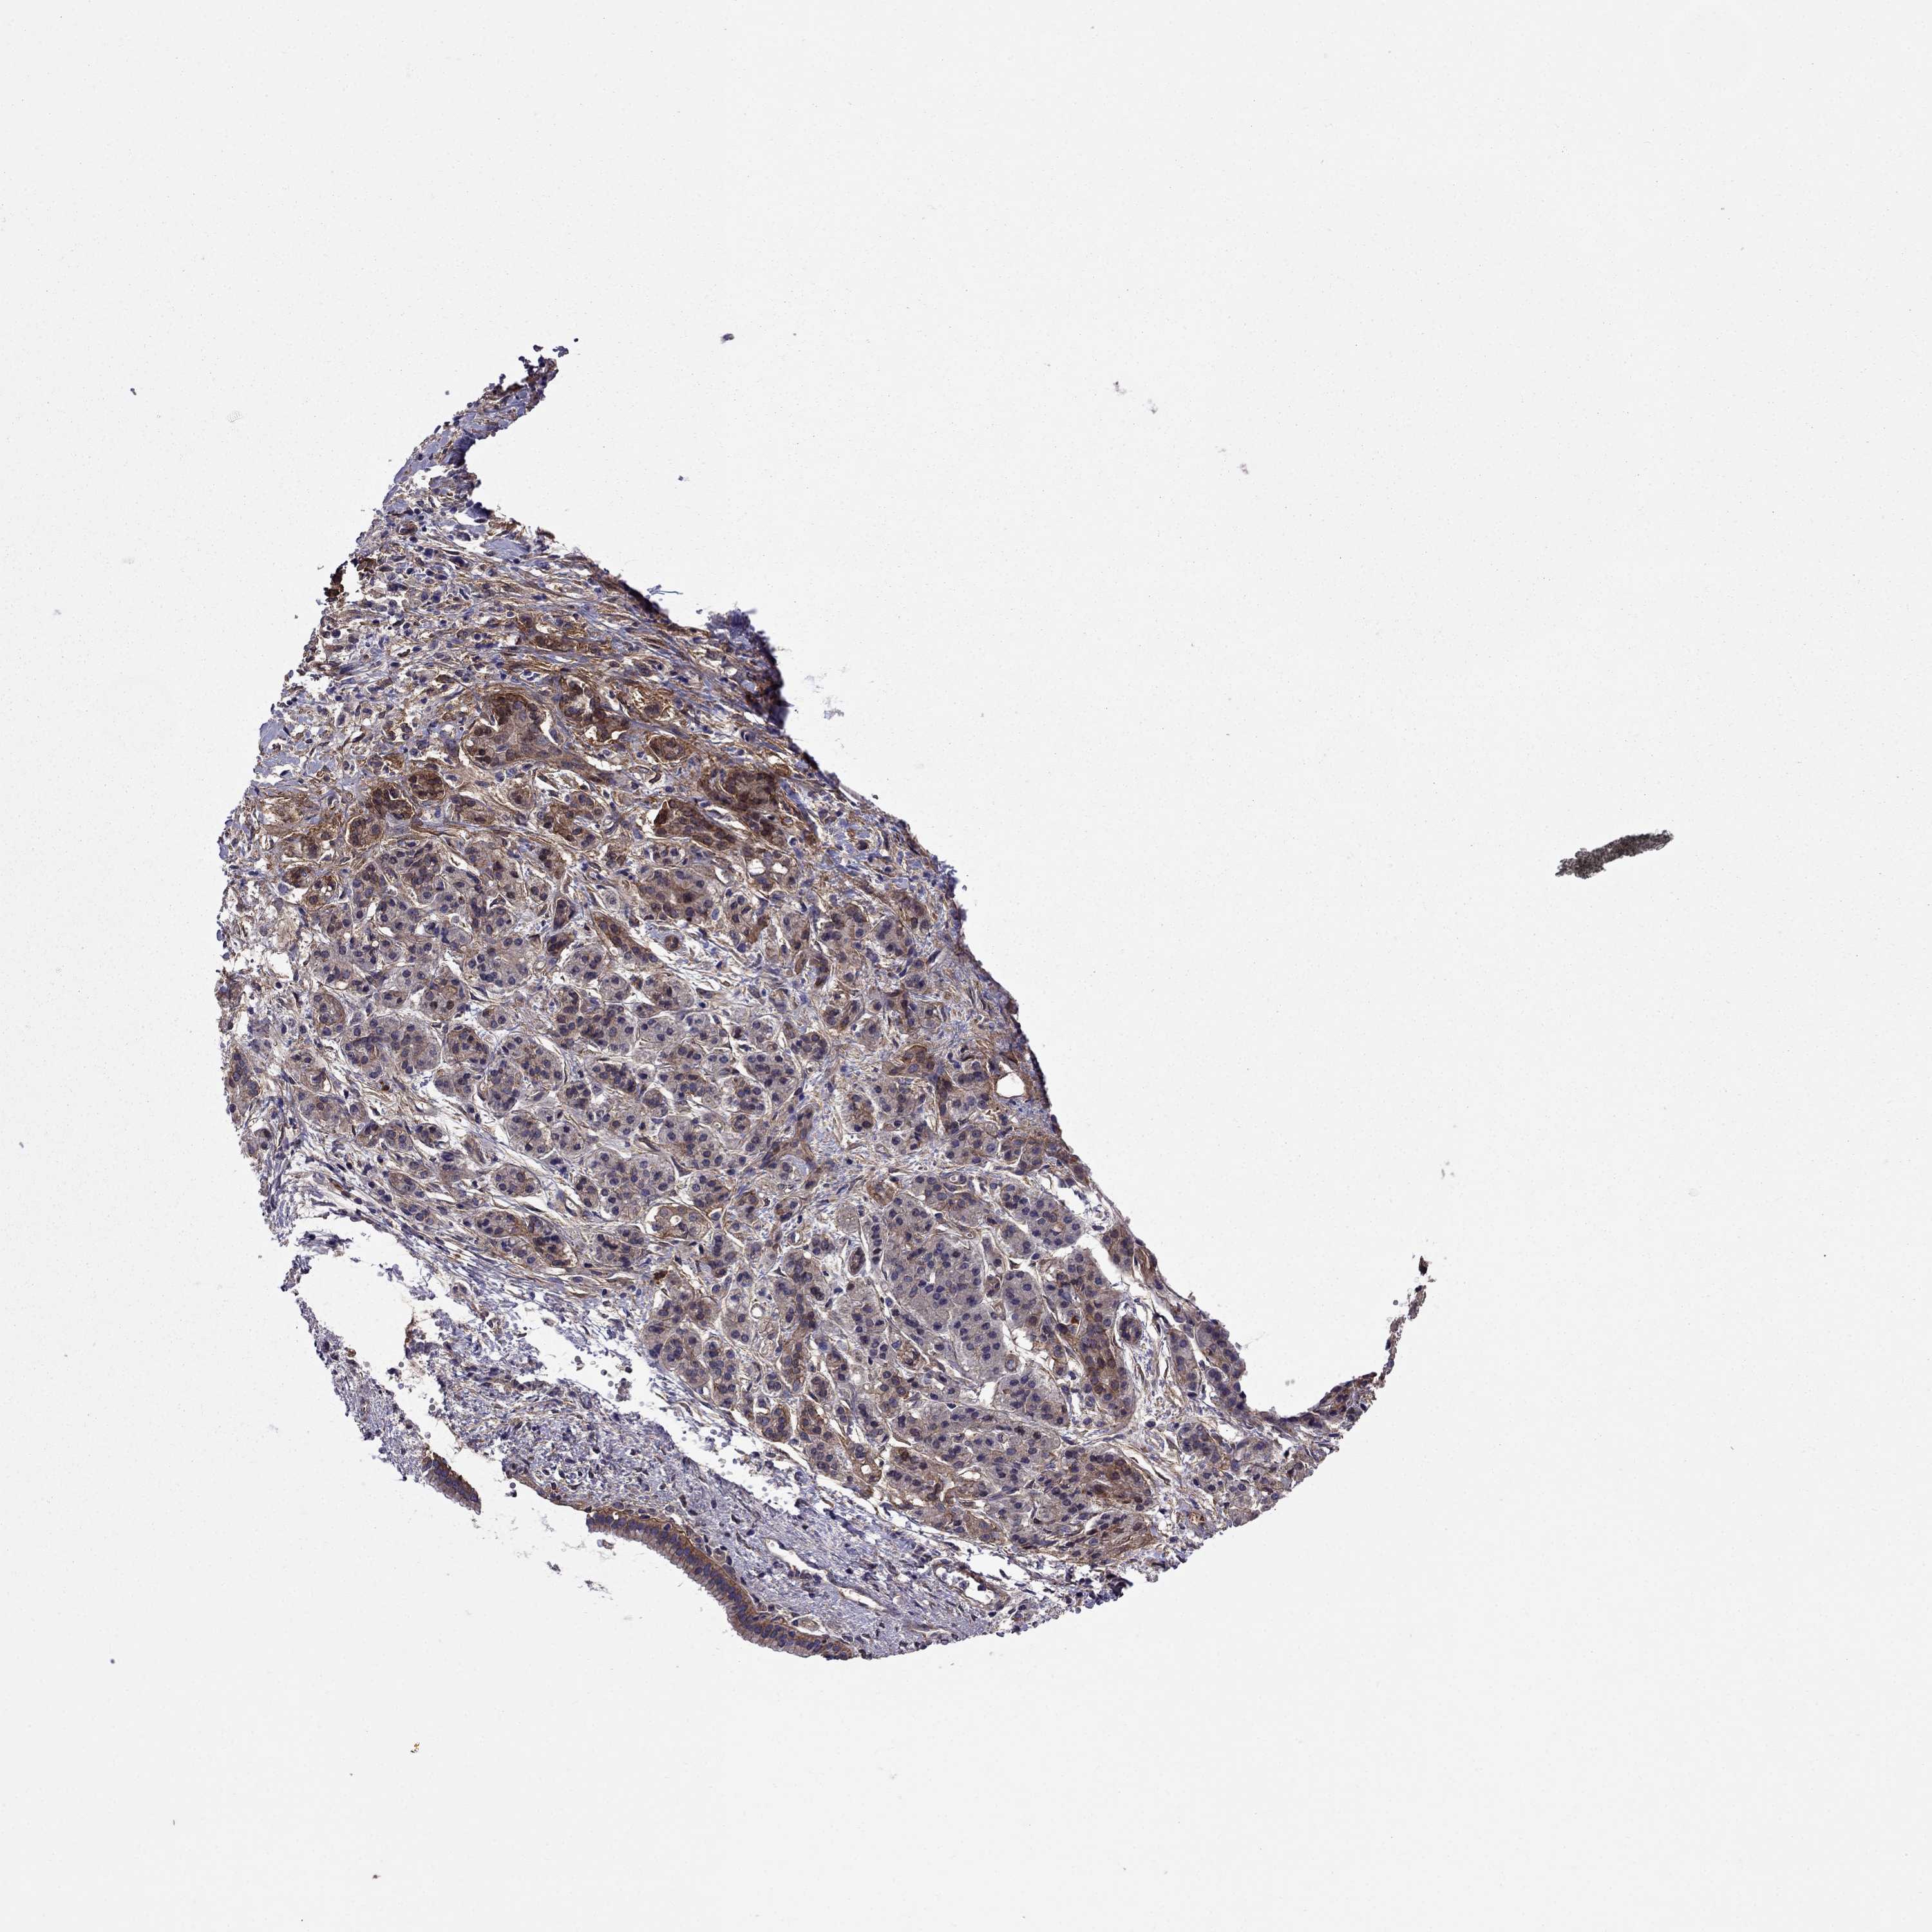

PANCREATIC CANCER - Protein expressioni

A mouse-over function shows sample information and annotation data. Click on an image to view it in a full screen mode. Samples can be filtered based on level of antibody staining by selecting one or several of the following categories: high, medium, low and not detected. The assay and annotation is described here.

Note that samples used for immunohistochemistry by the Human Protein Atlas do not correspond to samples in the TCGA dataset.

Antibody stainingi

Antibody staining in the annotated cell types in the current human tissue is reported as not detected, low, medium, or high, based on conventional immunohistochemistry profiling in selected tissues. This score is based on the combination of the staining intensity and fraction of stained cells.

Each image is clickable and will lead to virtual microscopy that enables deeper exploration of all samples and also displays staining intensity scores, fraction scores and subcellular localization as well as patient and tissue information for each sample.

Antibody HPA059297

Antibody HPA069003

Antibody CAB003434